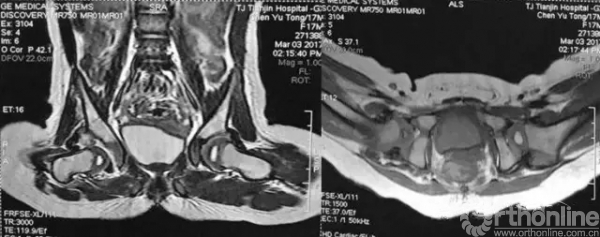

病例介绍:17个月女孩,因“步态异常”拍片发现右髋脱位。发育良好,无早产。体重10kg,家长诉偶尔可感到孩子“右髋部有响声”,否认家族髋关节疾患相关病史。查体:可独立行走,行走跛行。屈髋外展受限,Allis征阳性。入院后拍“骨盆正位片”及“双髋关节核磁”。行右下肢皮肤牵引10天,孩子配合皮肤牵引稍差。各项术前常规检查无手术禁忌,静吸复合麻醉下行“右髋脱位关节造影、试行闭合复位、人类位石膏裤固定”。

石膏裤固定后髋关节核磁与术中关节造影形态一致性良好,再次证实股骨头没有向后方脱位、头臼覆盖/对位满意。